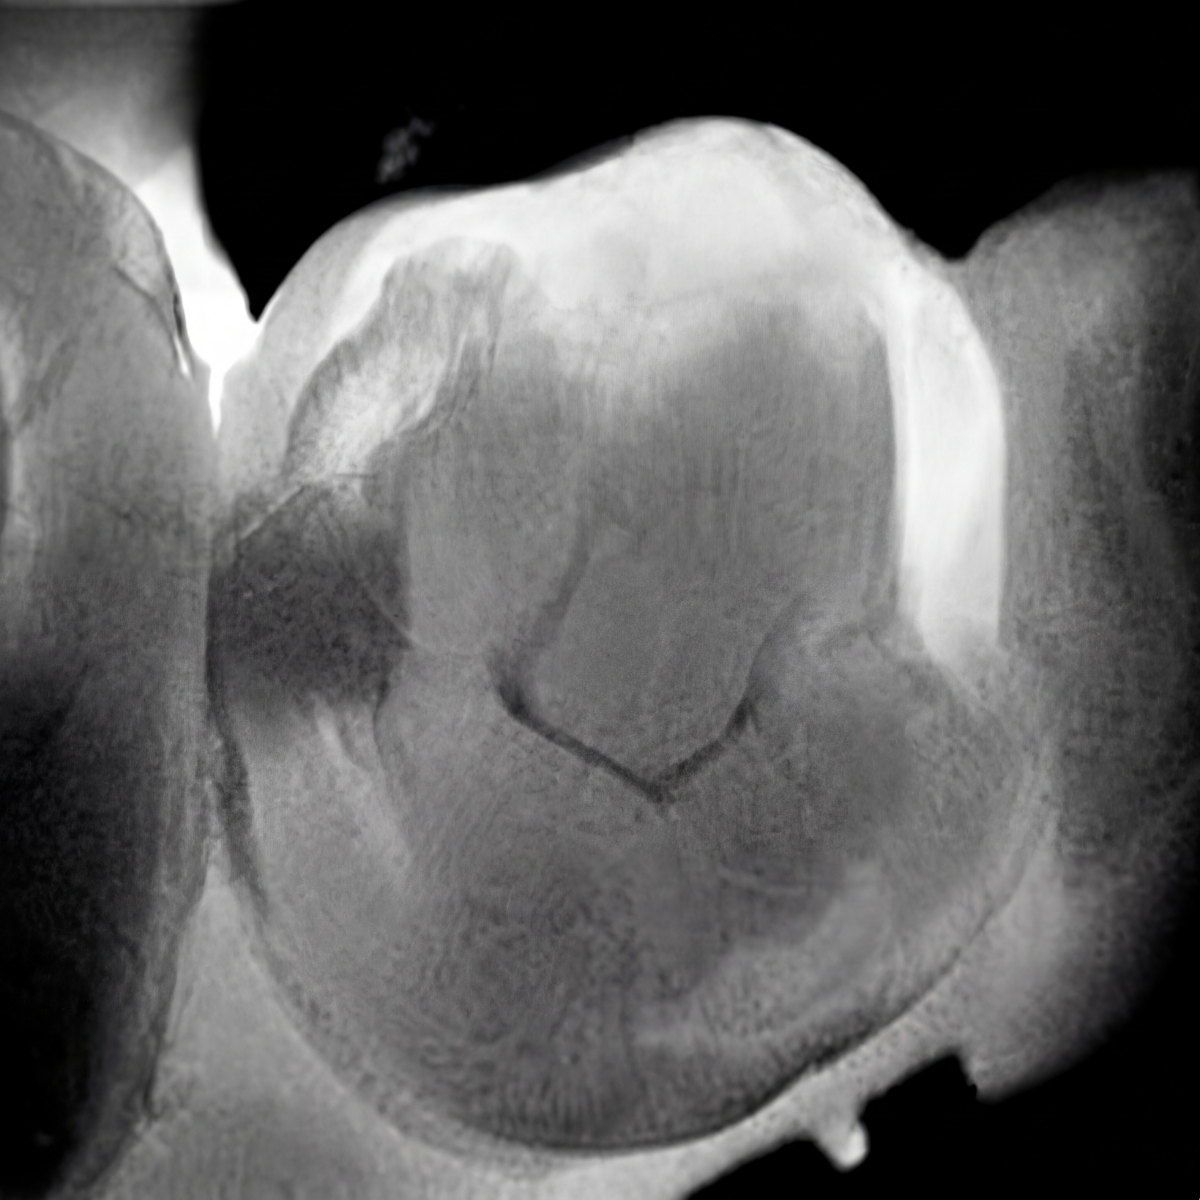

Lorsque cela est possible, nous utilisons la Diagnocam, une caméra permettant le diagnostic précoce des caries débutantes, de manière non irradiante.

Cette méthode repose sur la transillumination (laser à une longueur d’onde de 780 nm).